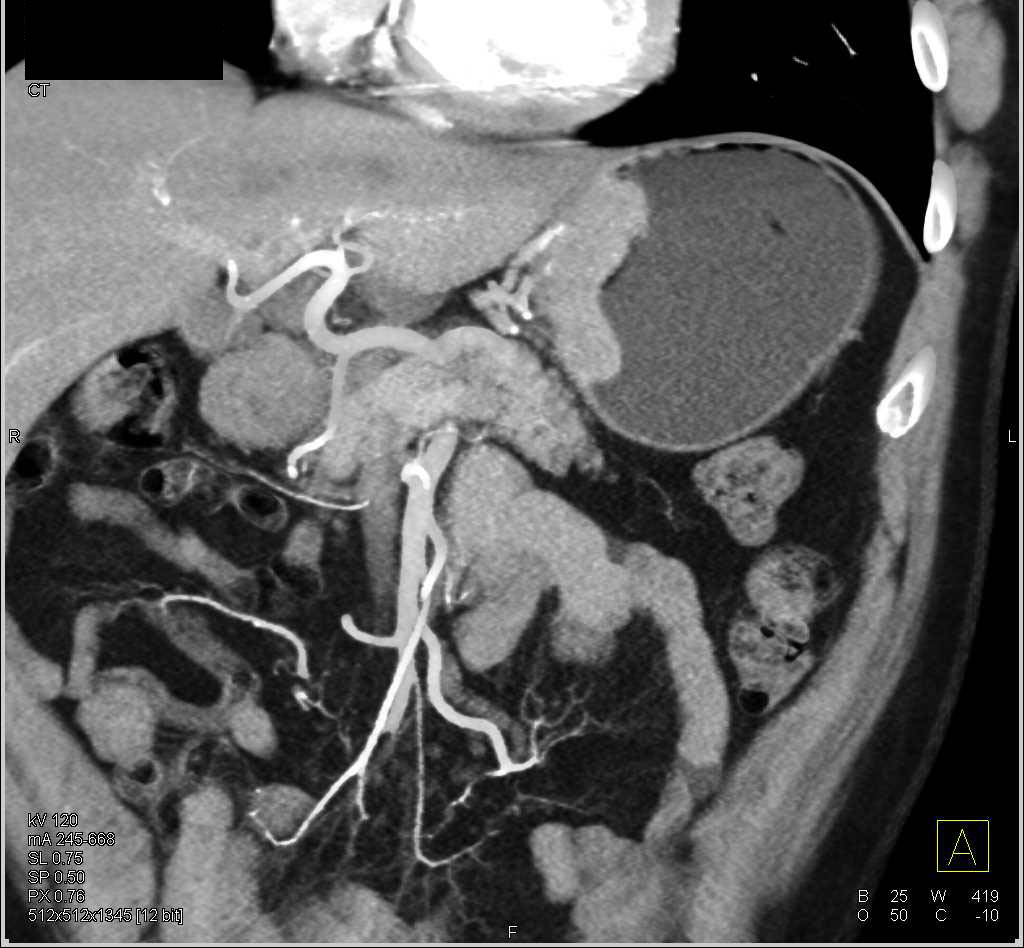

Lesser Sac Abscess Simulates an Unopacified Stomach